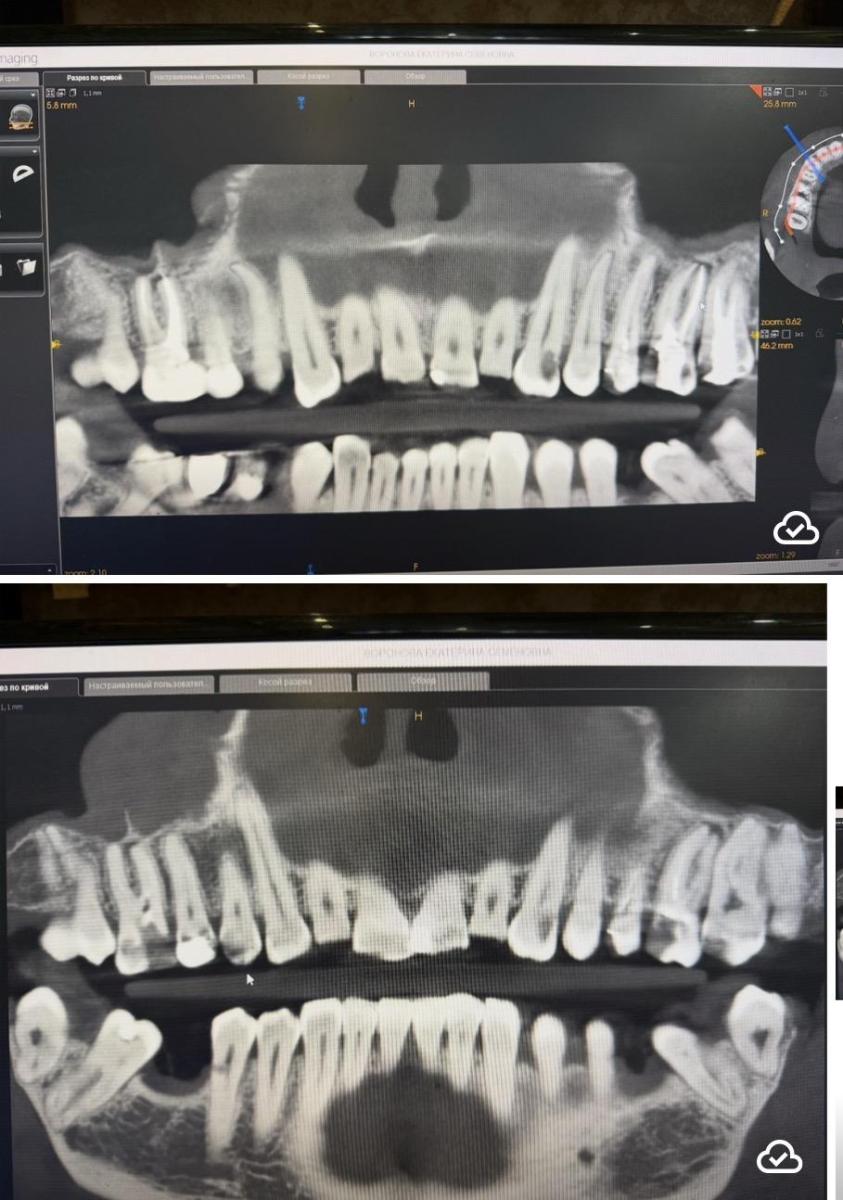

Юрий Жигурт, видна разница, кт в год разница.